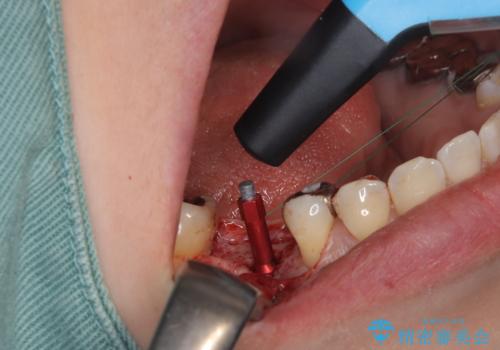

- 右下奥歯が虫歯で被せ物が取れてしまい、また噛めるようにしたいとのことで来院されました。

虫歯が大きく、歯を保存することが難しい状態でしたので、抜歯してインプラント治療を行うこととなりました。

骨の量は十分あったため、比較的短期間で治療は終了しました。